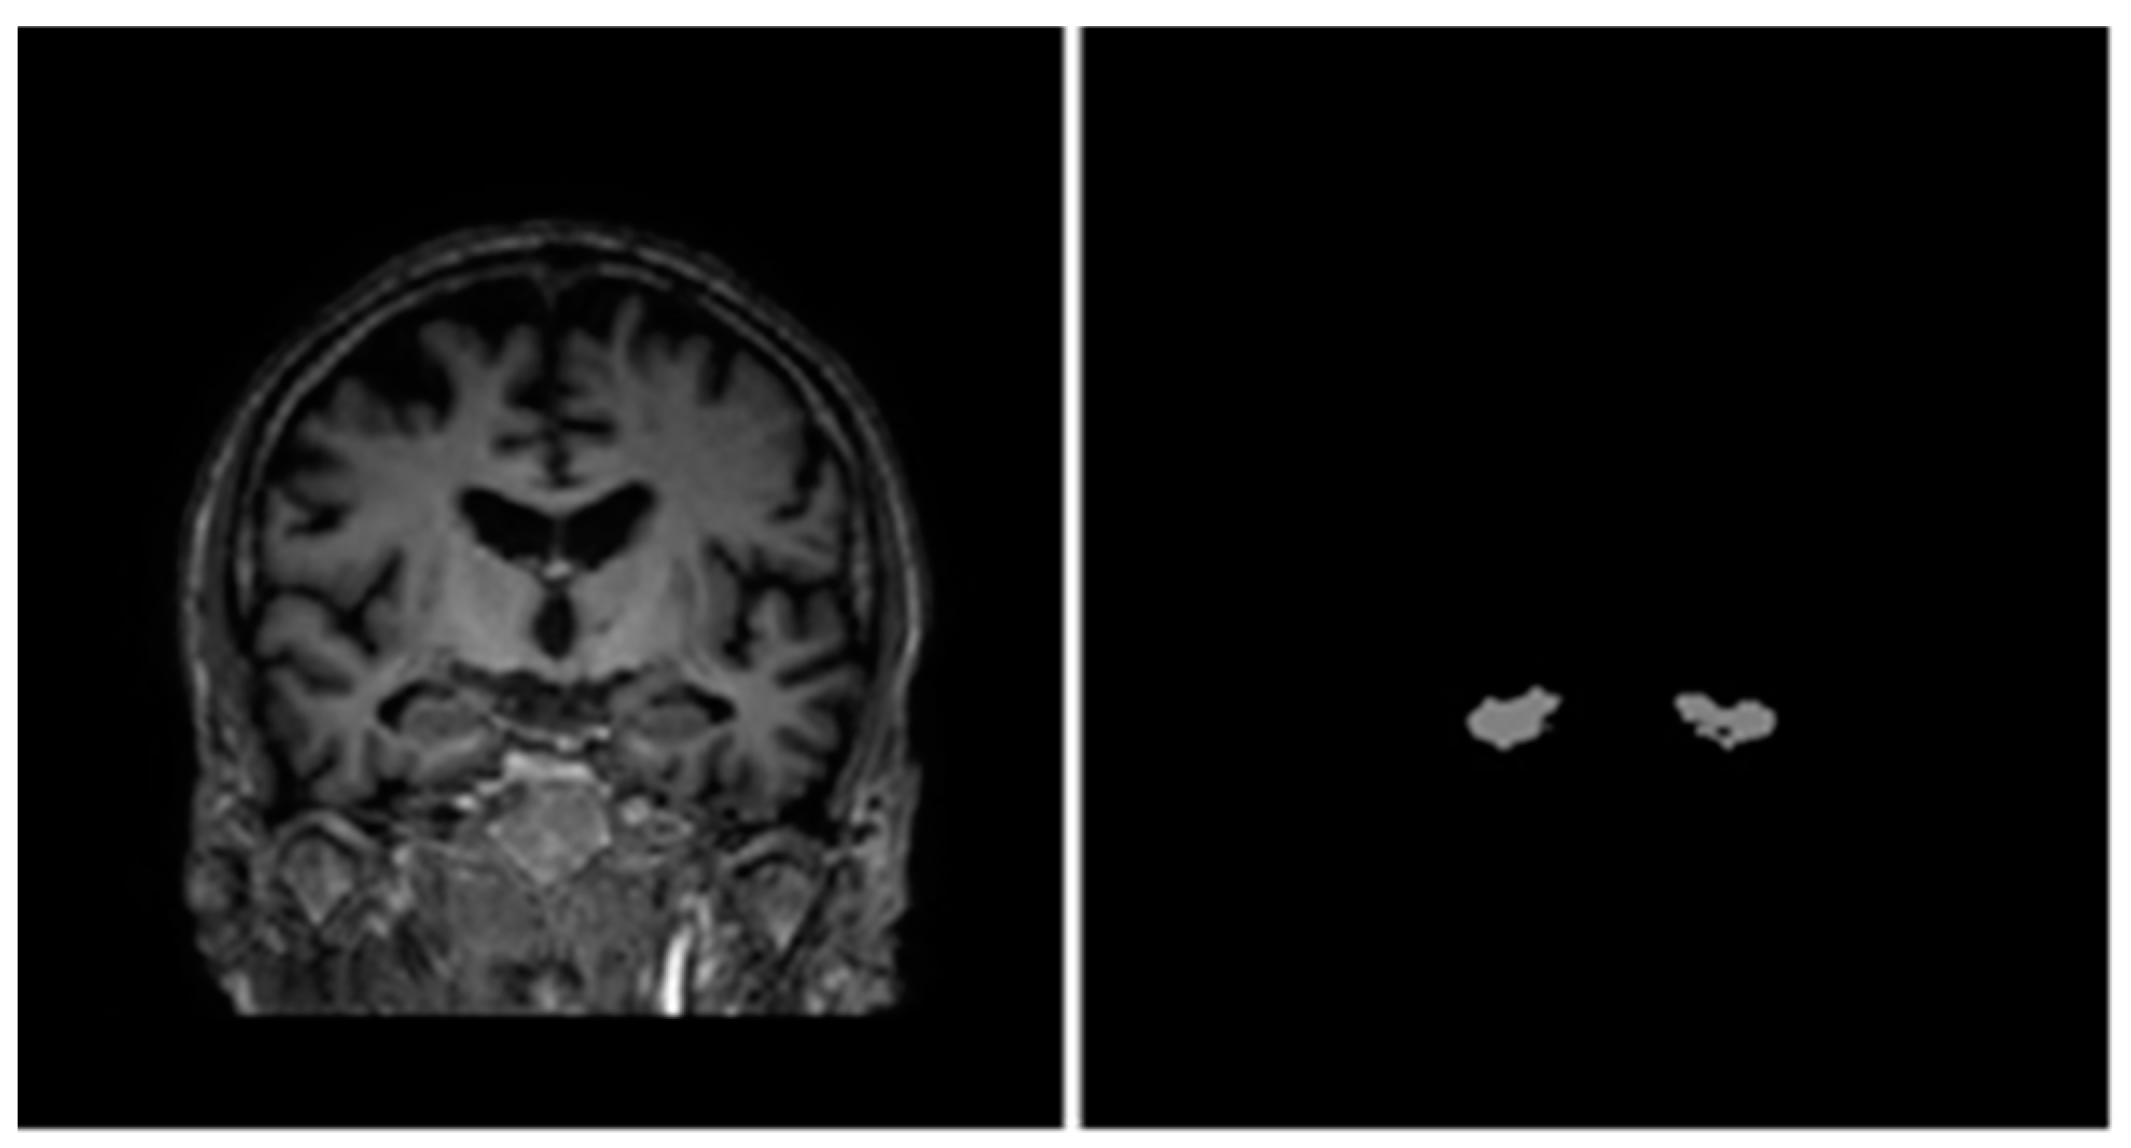

In 2013, a joint project between the European Alzheimer’s Disease Consortium (EADC) and Alzheimer’s Disease Neuroimaging Initiative (ADNI) came up with a standardized protocol for manual segmentation of the hippocampus from MRI scans known as the EADC-ADNI Harmonized Protocol (HarP) [32]. Further follow-up studies showed a significant increase in inter-rater intraclass correlation coefficient (ICC) when experts performing manual segmentations switched to using HarP [8,33]. HarP was also pathologically validated by comparison of HarP segmentations and post-mortem MRI scans of AD patients [34]. Upon establishing the validity of the HarP segmentation method, the EADC-ADNI team also recognized that many automated segmentation algorithms required a large sample of brain MRI volumes and their corresponding hippocampus segmentation masks (segmented with HarP) for training. Therefore, a dataset consisting of 135 brain MRI volumes complete with the benchmark HarP-segmented hippocampus masks was created for use in further research [35]. More information regarding the EADC-ADNI HarP data (including steps to download them) can be found in [36]. It should be noted that for every brain MRI volume, there were two hippocampus segmentation masks corresponding to the left and right hippocampus. A sample coronal view of a brain MRI volume and its corresponding combined hippocampus masks can be seen in Figure 4.

Figure 4.

Sample coronal view from brain MRI (left) and combined hippocampus masks (right) of subject 002_S_0559.

Each brain MRI volume was a cuboid with dimensions of 197 × 233 × 189; each voxel contained a real number representing the intensity of that voxel in the MRI scan. Note that unlike colored images with three RGB channels, each volume only had one channel because MRI scans produce grayscale images.